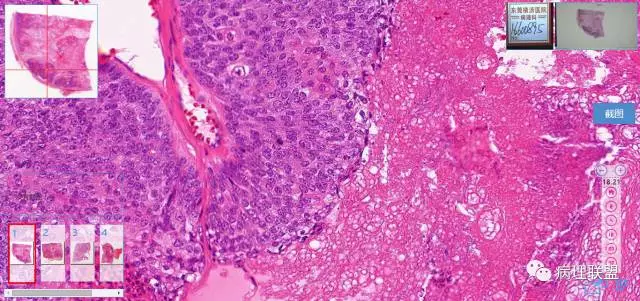

第一例

第一例和第二例病例我把典型图像压下来,是让我们以后注意,典型里找不典型,毛母质瘤主要由两种细胞构成,嗜碱细胞和影细胞构成,主要认识嗜碱细胞。

左老师,开始发的图片没有看到影细胞。最后加的图才看到了